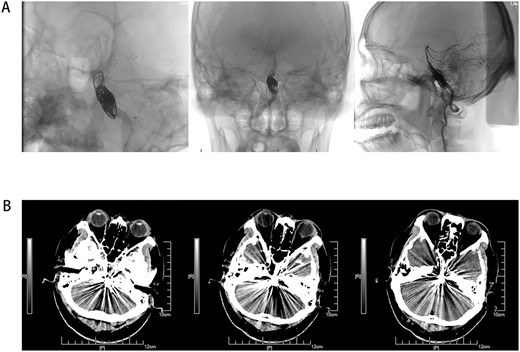

Male, AA, 44 years old, admitted in July 2022 with recurrent pain on the left side of the maxillofacial region for ~1 year. In the last 6 months, the dose of carbamazepine was increased to 300 mg three times daily, but the control of facial pain was still unsatisfactory, so the patient and his family numbers requested to be hospitalized for surgery. The patient had a history of hypertension for ~15 years. The maximum blood pressure was ~200/120 mmHg. The nifedipine controlled-release tablet was used to control his blood pressure by 30 mg daily, which is maintained at ~140/80 mmHg. The neurological examination on admission was unremarkable. TN was assessed as grade V according to the Bar row Neurological Institute classification. Magnetic Resonance Imaging (MRI) of the head suggests small ischemic focus in the pons and cerebellum; marked extending of the basilar artery (Fig. 1A–C). To clarify the etiology, doppler ultrasound of the carotid and vertebral arteries bilaterally revealed no atheromatous plaque or hemodynamics abnormalities. An electrocardiogram and cardiac function and cardiac ultrasound were performed. The results were normal. Biochemical tests for blood cell count, liver function, kidney function, and glucose test revealed no abnormalities. The Digital subtraction angiography (DSA) was given to the patient (Fig. 2A and B). Antiplatelet aggregation therapy with a combination of clopidogrel and aspirin was used before operation. The DSA displayed the VBD, the VBD was length 2.5 cm and width 9 mm, its path was tortuous and deviated to the left. Normal blood flow in the middle venous phase of the imaging was normal. Stent-assisted interventional embolization was chosen. A suitable coil was selected to form basket by EV3 (20 mm*50 cm, Medtronic, USA) and the stent catheter was withdrawn and repositioned through the coil into the right posterior cerebral artery. Release stent 1: LEO (5.5 mm*60 mm, LEO, USA), then choose the appropriate ring (14 mm*30 cm, 13 mm*30 cm, 12 mm*30 cm, 10 mm*30 cm, Taijie Weiye, China) to occlude the dilated artery (Fig. 3A). Postoperatively, we scanned the Computed Tomography (CT) (Fig. 3A), the TN was completely relieved, but there was residual left-sided facial palsy with a House-Brackmann grade IV and a grade III right limb muscle strength. Systematic treatment was operated at the rehabilitation unit, once the condition was stabilized. At 3 months post-operative follow-up the patient showed significant improvement in muscle strength in the right limb, with muscle strength grade V− and significant improvement in facial palsy, which was graded House-Brackmann grade II.

(A) DSA-lateral, (B) DSA-Frontal. Basilar trunk dilation up to 9 mm of diameter and extended over 25 mm of length with a tortuous and deviated path to the left side.